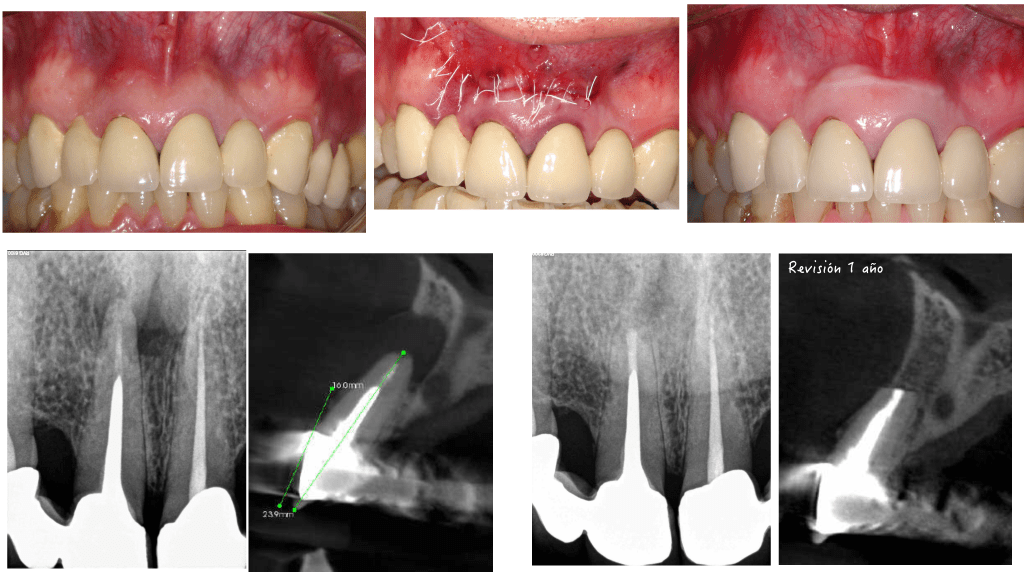

En esta ocasión, tratamos un caso con una reabsorción apical de la raíz distal de un molar inferior. Casos, con aparente no tan buen pronóstico, pero que en nuestra experiencia, vemos que son predecibles si los manejamos de forma correcta. un saludo.

En ese caso clínico vemos como podemos manejar una gran perforación en furca con buenos resultado.

Subo este video con varios casos con «aparente mal pronóstico» , pero que si lo abordamos correctamente, serán casos con un pronóstico muy favorable, pero necesitamos FORMACIÓN Y EQUIPO DE TRABAJO.